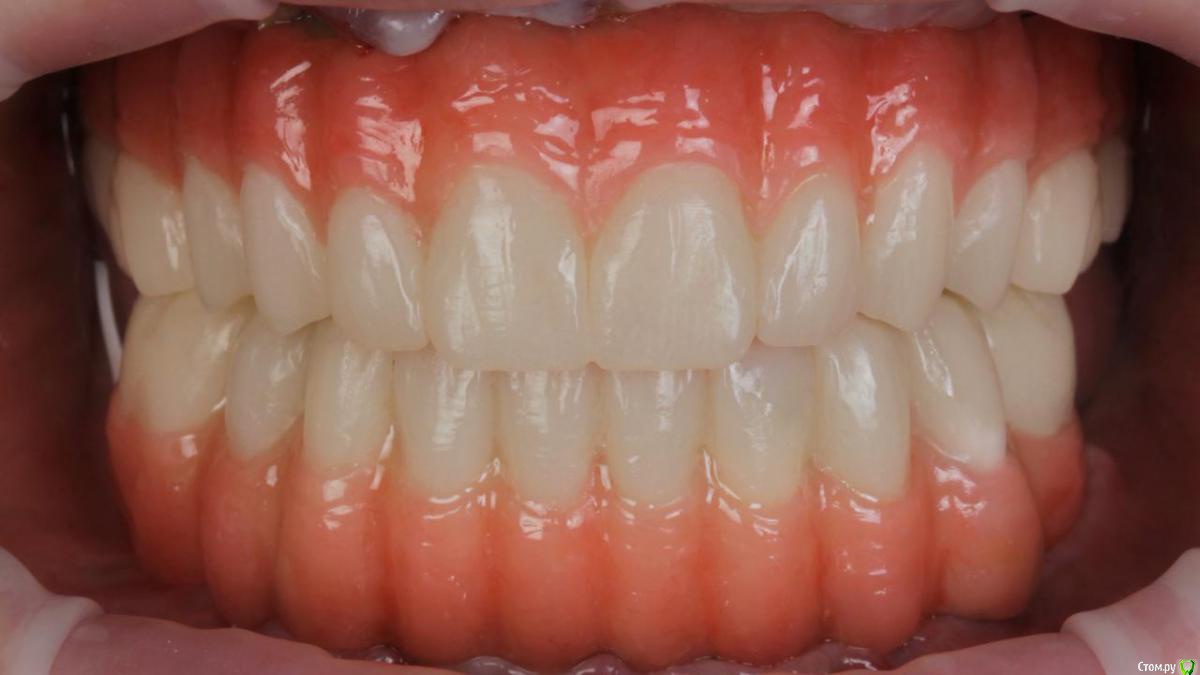

Bier Опубликовано 10 февраля, 2020 Поделиться Опубликовано 10 февраля, 2020 Хирургия в седации 3,5 часа + редукция гребня. По шаблону под пилот. Все мультиюниты были заранее выбраны техником и четко сели.Временные армированные протезы (лазерное спекание) 8 Ссылка на комментарий

Bier Опубликовано 11 февраля, 2020 Автор Поделиться Опубликовано 11 февраля, 2020 А какую финальную конструкцию планируете?Металло композит или металлический каркас с индивидуальными коронками из керамики. Скорее всего на одну челюсть так, другую так. Ссылка на комментарий